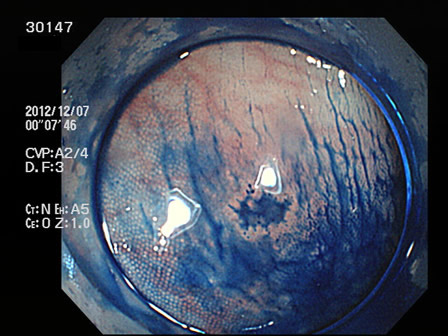

上記100名より抽出した平坦・陥凹型腺腫(=癌化の危険が高いが見落としやすい病変)の内視鏡写真